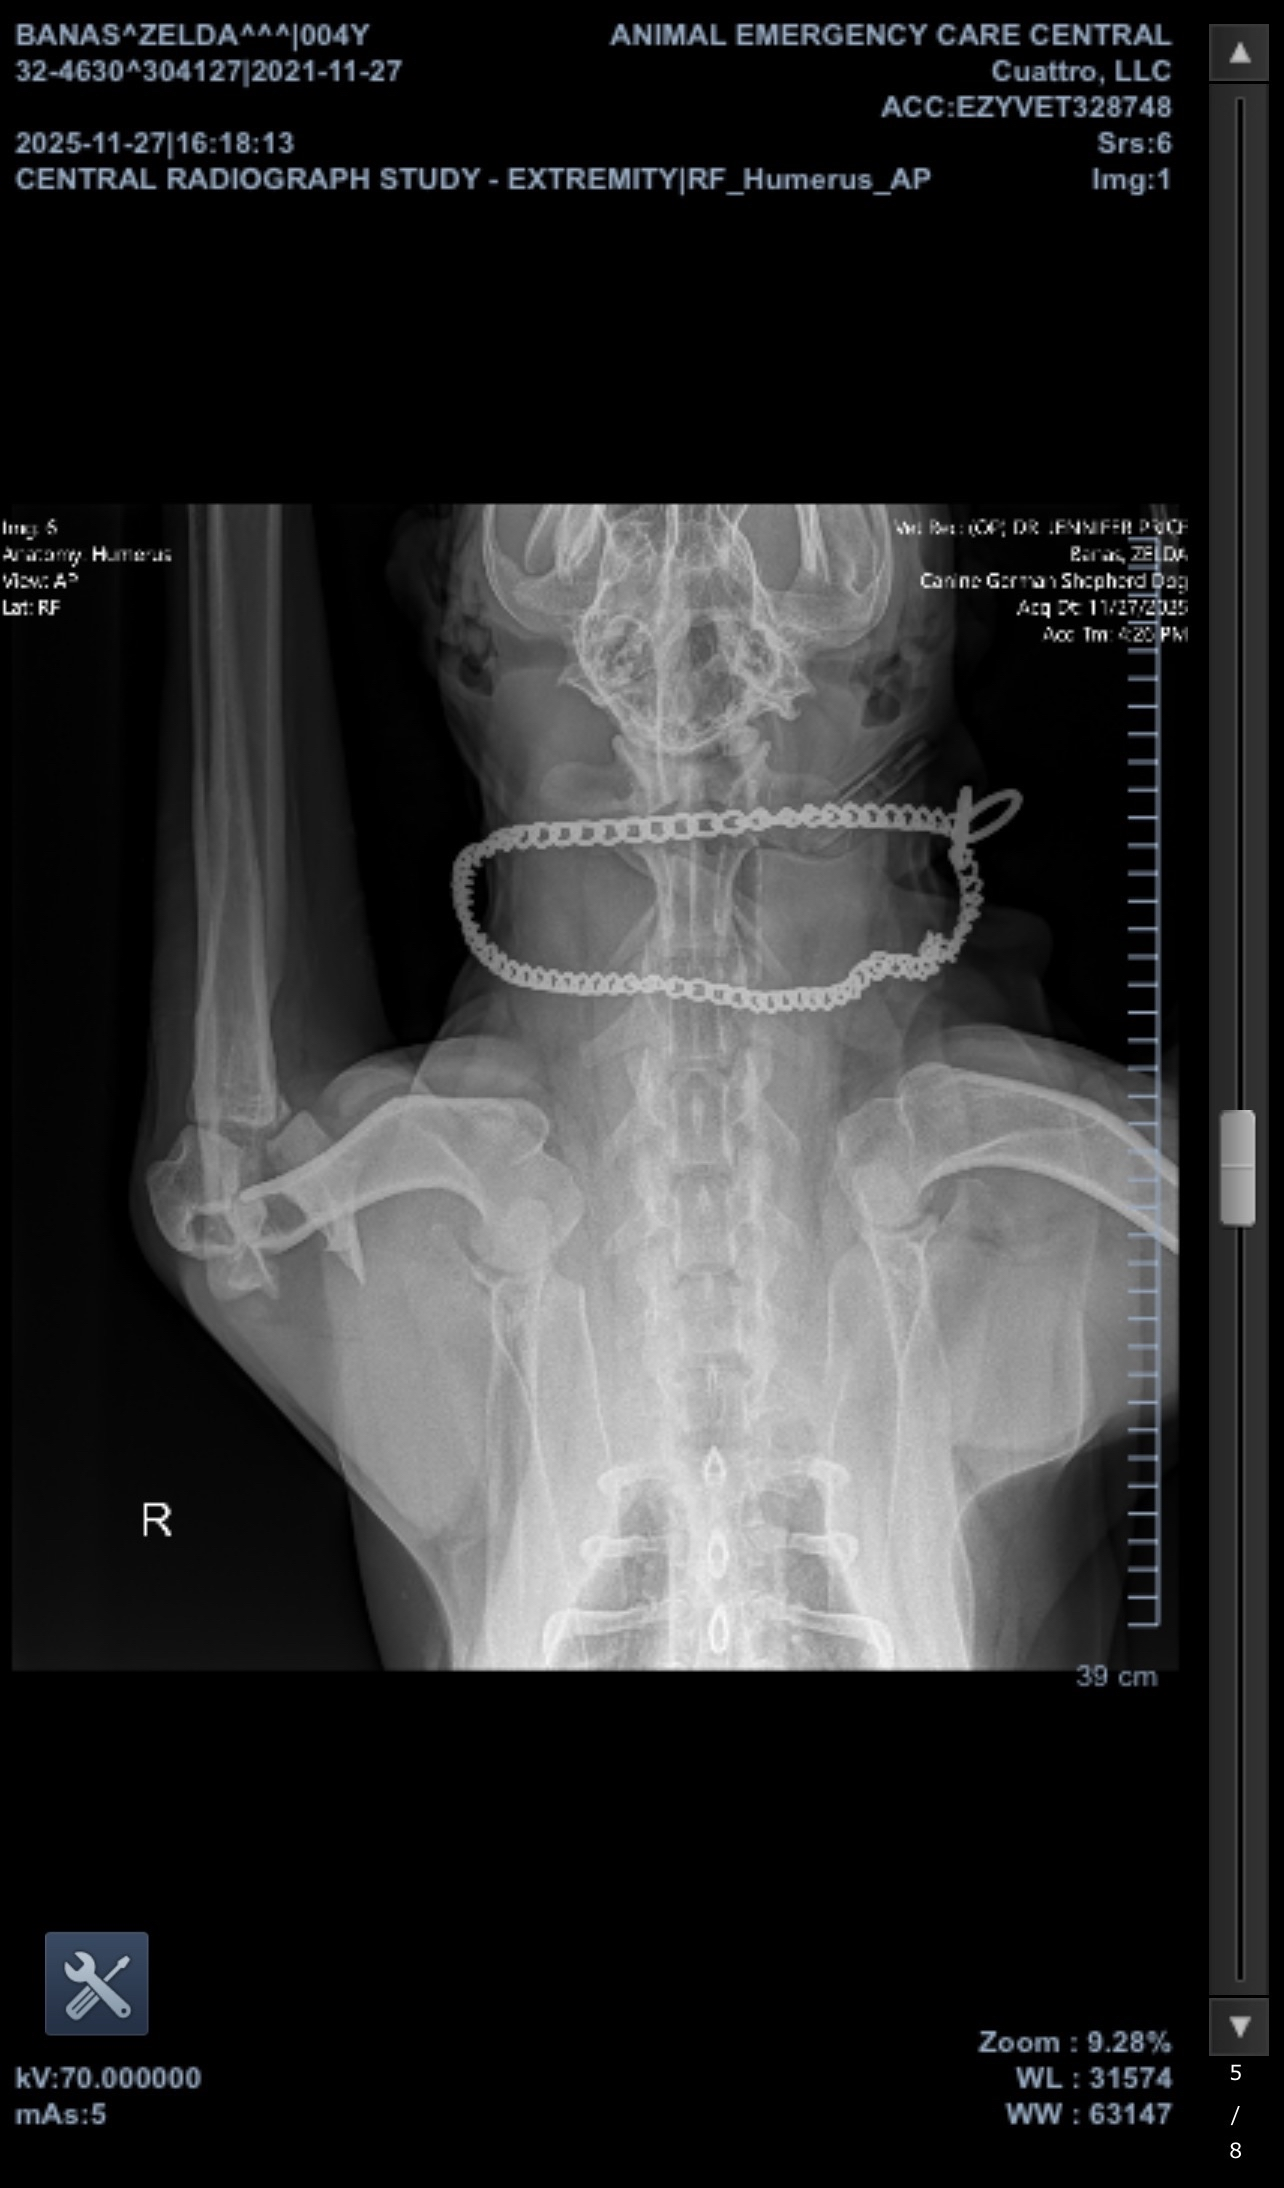

On Thanksgiving, our family’s world turned upside down. While playing our daily game of fetch, our beloved dog Zelda landed wrong on her right leg and snapped her elbow. The pain was immediate and intense—she was immobilized and crying out, and we rushed her to the emergency vet. The x-rays showed catastrophic damage, and we were told she would need surgery as soon as possible.